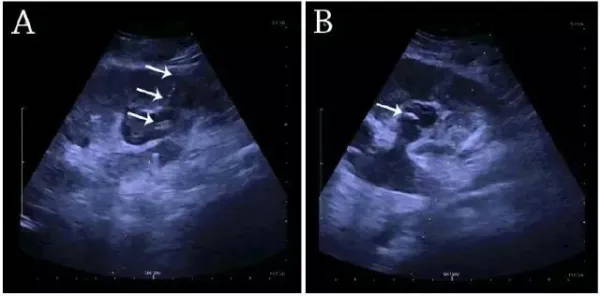

Kidney biopsy, percutaneous nephrostomy, or abscess drainage can be performed under ultrasound guidance. In the past, thermal ablation of renal tumors was guided by CT, because ultrasound-guided intervention was difficult to clearly display the intestinal distribution, resulting in a higher risk of peripheral intestinal injury. However, the latest guidelines for renal interventional therapy recommend ultrasound guidance as the preferred choice for radiofrequency, microwave, and cryoablation.

(A) Percutaneous nephrostomy with a fistula placed through the renal calyx into the hydronephrosis at the lower pole of the kidney. (B) Pigtail catheter placed in the calyceal dilatation. White arrows: fistula and pigtail catheter.

Percutaneous nephrostomy and abscess drainage can be performed using the one-step or Seldinger technique. Clinicians can choose one-step or Seldinger techniques based on preference, experience, and equipment conditions.